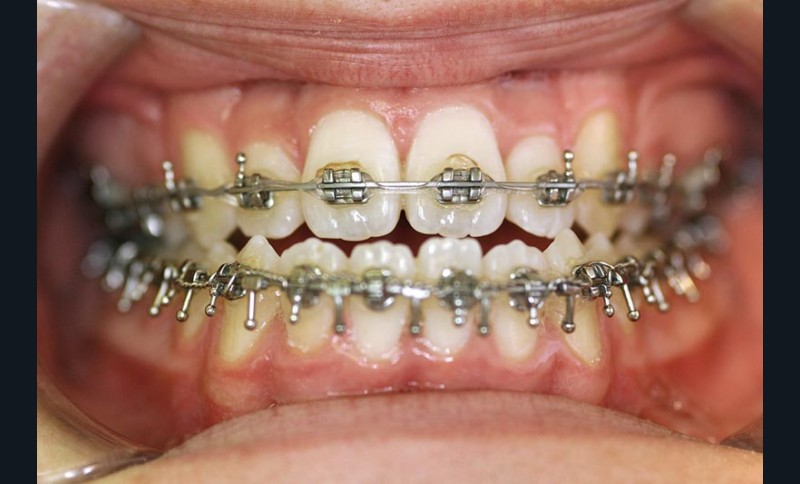

Une pause thérapeutique est ensuite entamée jusqu’à la fin de croissance soit 18 ans. Une poursuite du traitement par préparation secondaire à la chirurgie orthognathique bimaxillaire est programmée.

Les mouvements de décompensations sagittales et transversales sont réalisés à l’aide des tractions inter-arcades. La réévaluation céphalométrique et l’analyse des moulages confirment l’indication d’une chirurgie maxillaire de propulsion et d’une chirurgie mandibulaire par clivage bilatéral des branches montantes pour un recul mandibulaire modéré accompagné d’une génioplastie bidimensionnelle élargie qui rappelle la technique de Chin Wing.